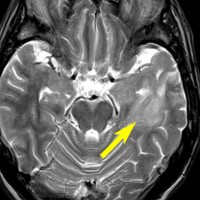

80代の女性に偶然見つかったものです。右の島のグリオーマ insular gliomaで,ガドリニウム増強されないびまん性グリオーマです。右側は2ヶ月半後のMRIで,とても早く広がっていますので,生検術をしました。組織診断は,壊死や微小血管増生はなく,びまん性星細胞腫グレード2でした。TERT promotor mutant, IDH1 WT, IDH2 WT, H3F3A-K27 WT, H3F3A-G34 WT, m HIST1H3B WT, 1p/19q intact, CDKN2A/2B negativeです。

この例は,molecular GBMつまり,glioblastoma IDH-WT WHO grade 4と診断されます。